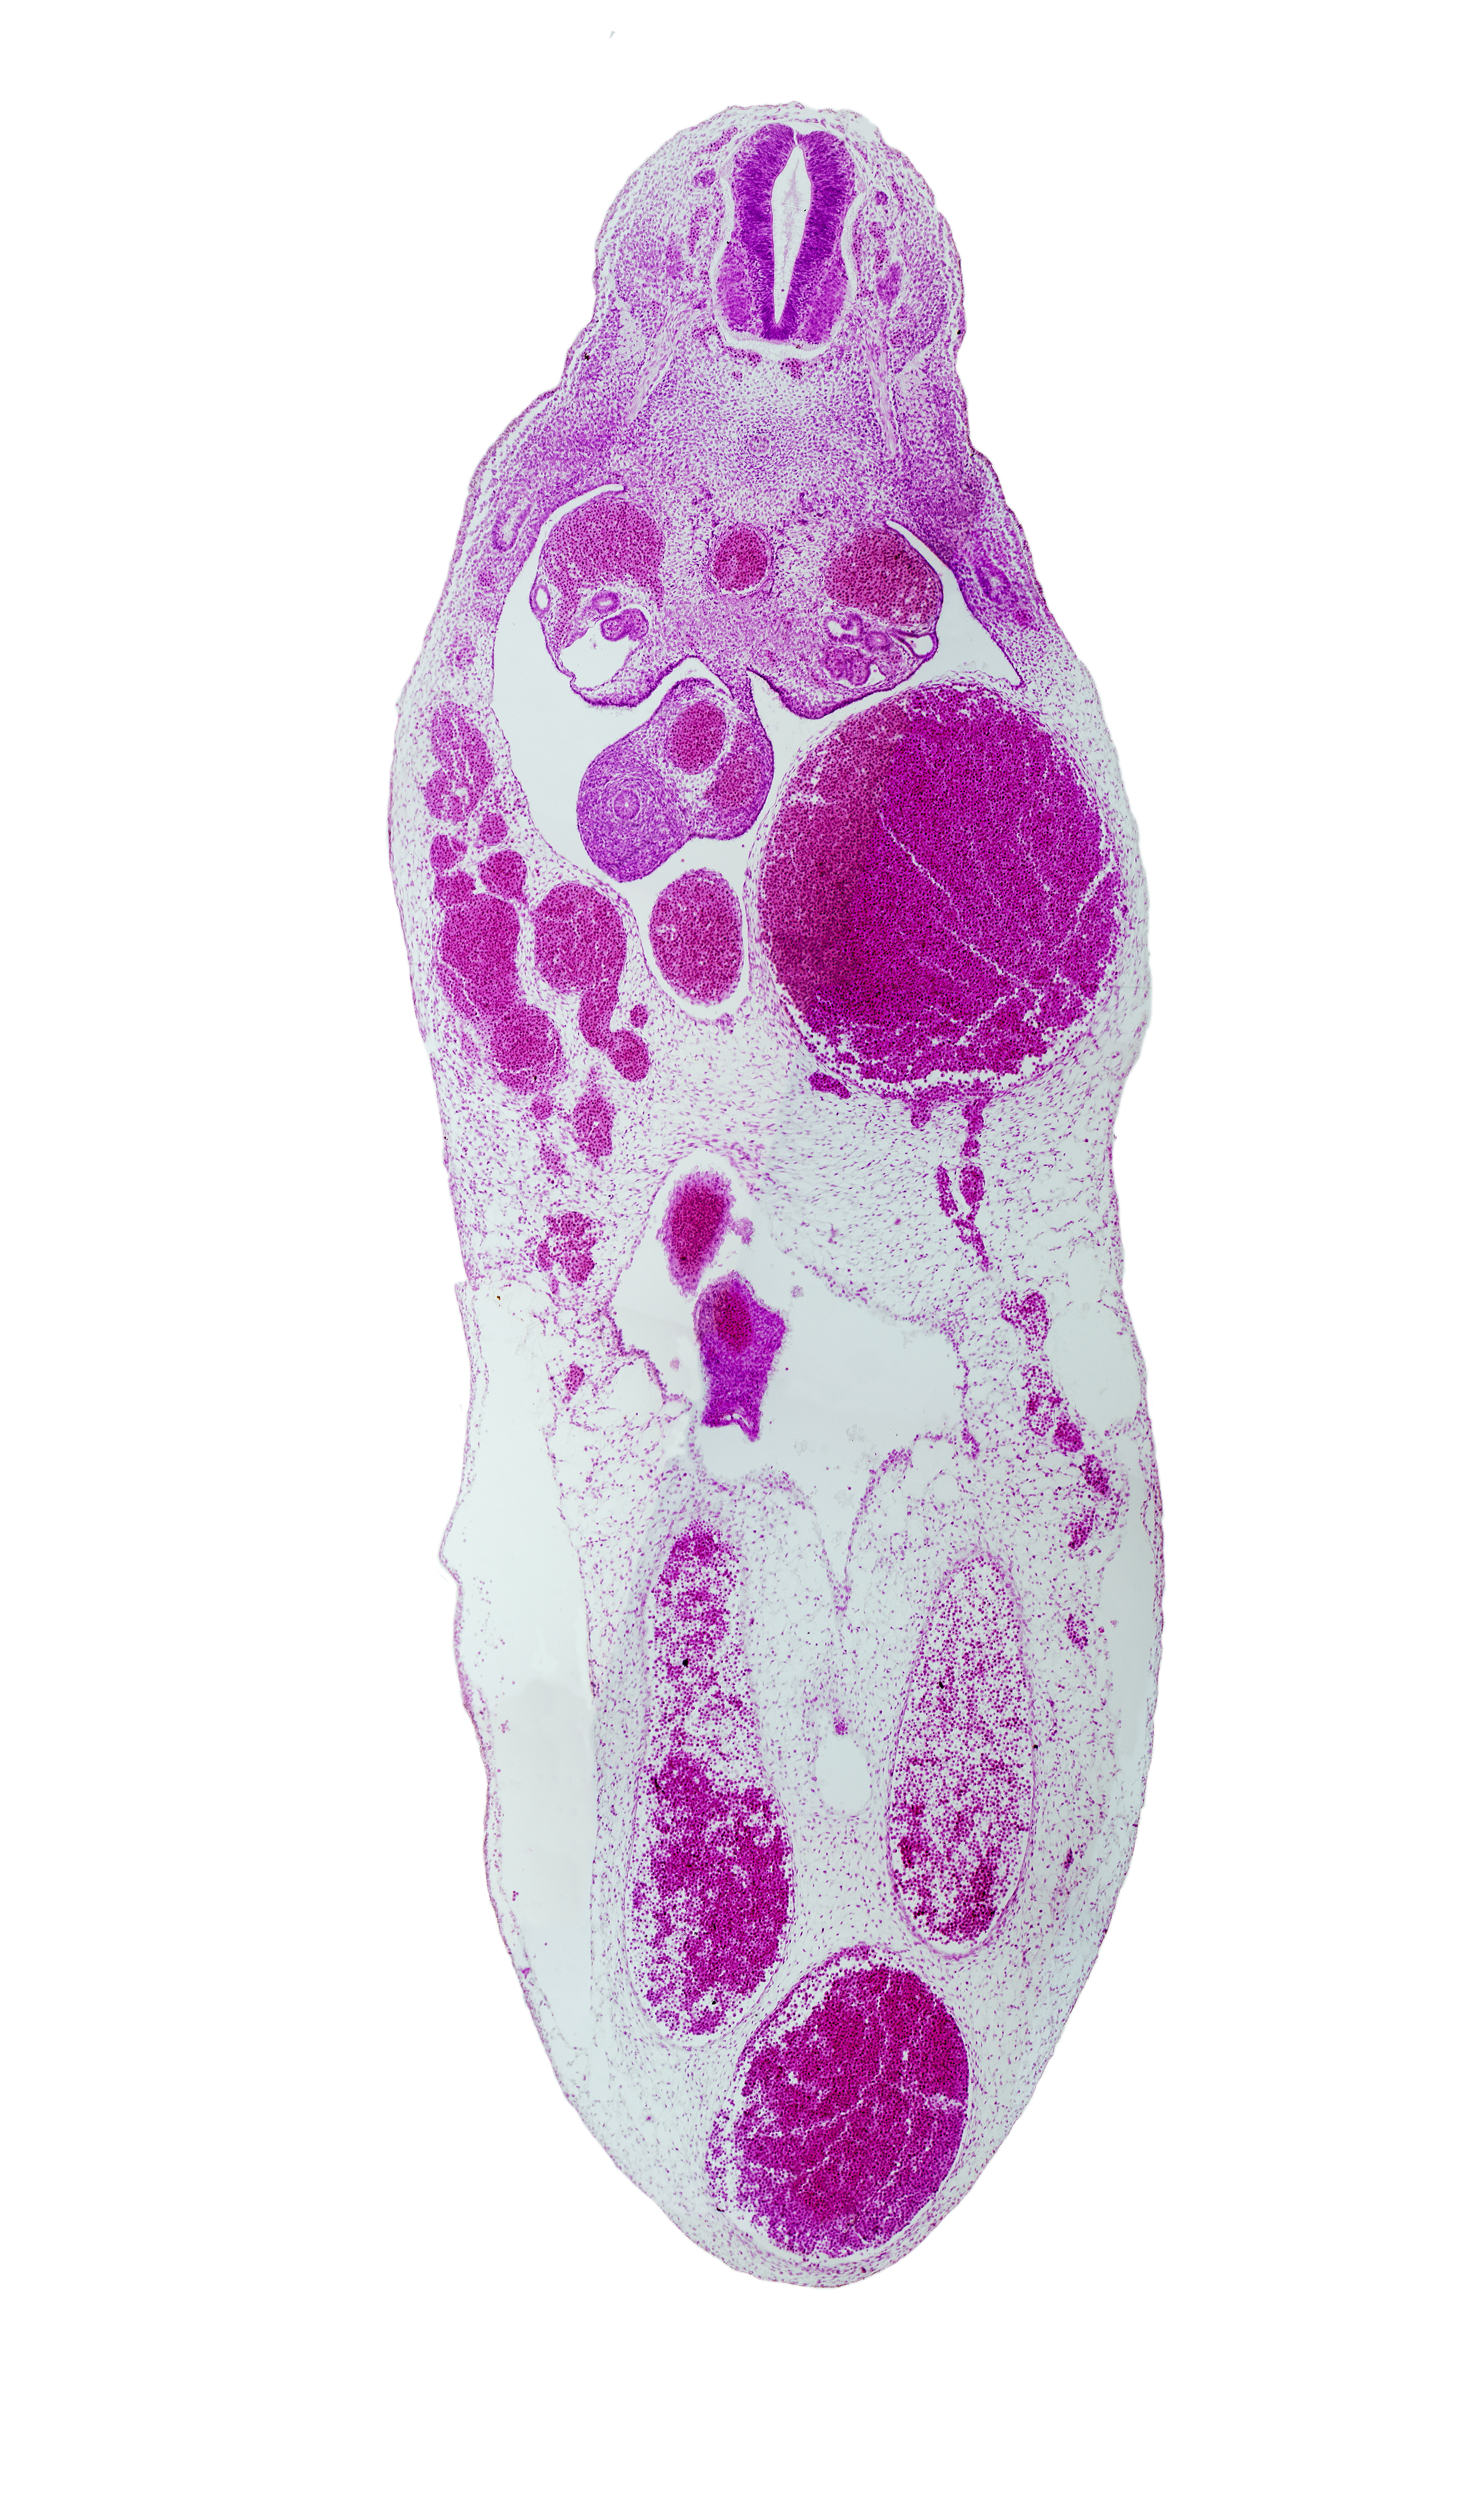

Carnegie Embryo #721 | Location: 19-03-06

Keywords: aorta, cephalic edge of T-7 spinal ganglion, left umbilical artery, left umbilical vein (congested), mesonephric duct, midgut, right umbilical artery, right umbilical vein, superior mesenteric artery, umbilical coelom, umbilical cord, umbilical intestinal loop, umbilical vein, vitelline (omphalomesenteric) artery, vitelline (omphalomesenteric) vein

Source: The Virtual Human Embryo.